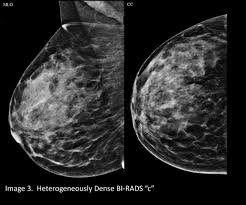

What does breast cancer look like on a mammogram? Screening mammograms have been used since the 1980s. On mammograms, dense breast tissue looks white. Bright spots on a mammogram that look like potential tumors could turn out to be overlapping tissues or a blood vessel folding over on itself, friedewald said. The outer edges of these cells look fuzzy or spiky (called spiculated). Moose & doc breast cancer, 21 may 2018. It is also an anatomic test, which means cancer is detected based on changes in how the breast anatomy looks. Food and drug administration in 2011. After a mammogram that didn't show anything, and a sonogram that found the lump, i was diagnosed with stage 2 breast cancer. Treatment typically involves some type of surgery and depends upon the staging of the. What does breast cancer look like on a mammogram? It appears to be developing in a concentric pattern. A mammogram can show breast changes such as calcifications, masses, or other symptoms that might be cancer.